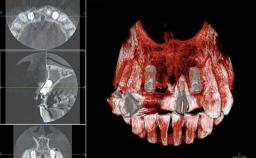

This 20-year-old woman was referred to our department in July 2006. Four months earlier, she had experienced dental trauma to the anterior maxilla when traveling in South America. The emergency treatment included emergency root canal treatment of teeth 12 and 11. Tooth 21 was also subjected to endodontic treatment later. At the initial examination, the patient was not in pain but reported increased mobility of tooth 12. The clinical examination revealed a high smile line, medium thickness of the soft tissue, and rectangular tooth forms. Discoloration of tooth 12 was evident. The periapical radiograph provided by the referring dentist indicated a fracture line at both teeth 12 and 11. A cone-beam computed tomography (CBCT) scan confirmed these fractures. No pathology was found to be associated with tooth 21.